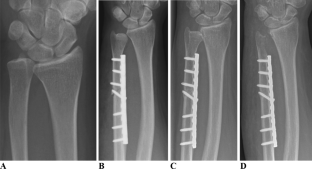

Fig. 4